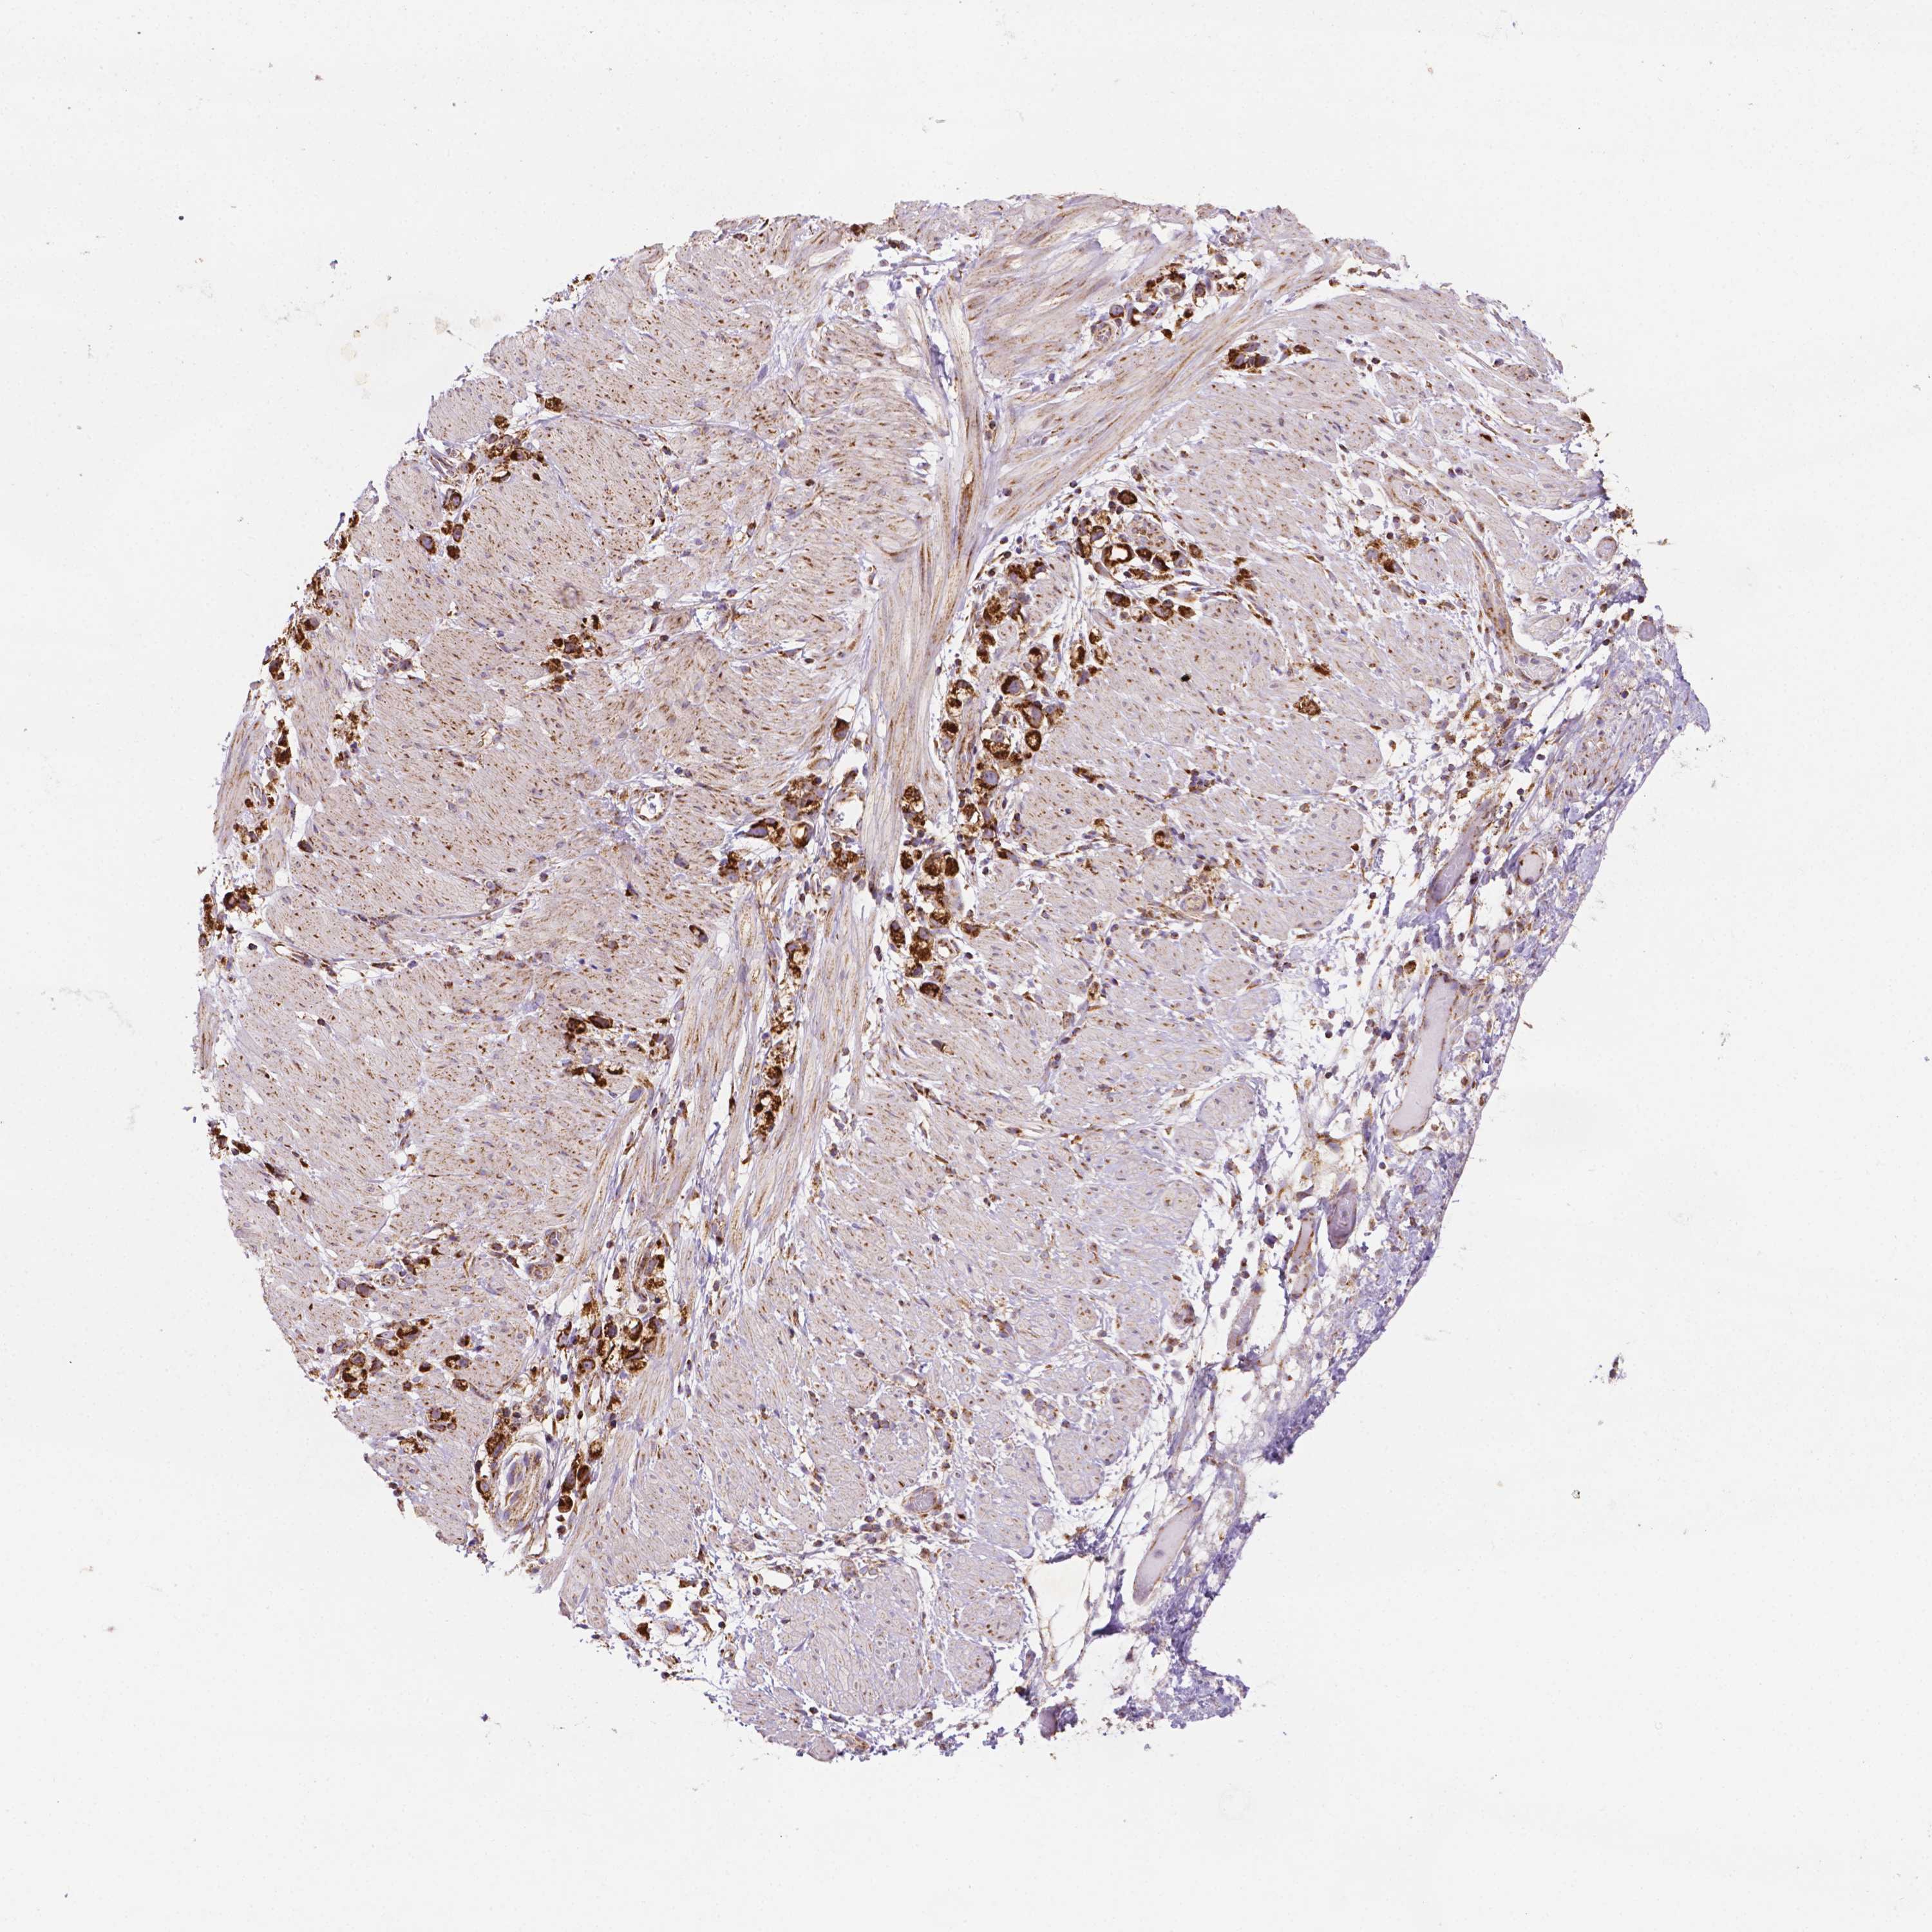

STOMACH CANCER - Protein expressioni

A mouse-over function shows sample information and annotation data. Click on an image to view it in a full screen mode. Samples can be filtered based on level of antibody staining by selecting one or several of the following categories: high, medium, low and not detected. The assay and annotation is described here.

Note that samples used for immunohistochemistry by the Human Protein Atlas do not correspond to samples in the TCGA dataset.

Antibody stainingi

Antibody staining in the annotated cell types in the current human tissue is reported as not detected, low, medium, or high, based on conventional immunohistochemistry profiling in selected tissues. This score is based on the combination of the staining intensity and fraction of stained cells.

Each image is clickable and will lead to virtual microscopy that enables deeper exploration of all samples and also displays staining intensity scores, fraction scores and subcellular localization as well as patient and tissue information for each sample.

Antibody HPA067682

Staining

High

Medium

Low

Not detected

Intensity

Strong

Moderate

Weak

Negative

Quantity

>75%

75%-25%

<25%

None

Location

Nuclear

Cytoplasmic/membranous

Cytoplasmic/membranous,nuclear

Adenocarcinoma, NOS